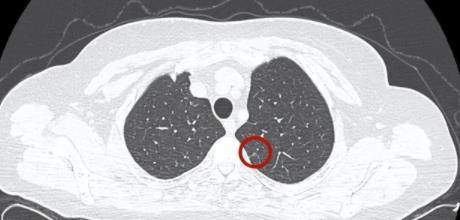

體檢查出的“結(jié)節(jié)”,一定會發(fā)展為癌癥嗎?

正值第29屆全國腫瘤防治宣傳周,腫瘤相關(guān)話題成為關(guān)注焦點(diǎn)。近些年,不少人在體檢中被查出“結(jié)節(jié)”,一些人還為此提心吊膽,擔(dān)心有癌變風(fēng)險......